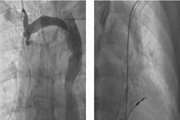

تیکاگرلور یا کلوپیدوگرل؟ انتخاب بهتر برای بیماران قلبی پایدار بعد از استنت

یک متاآنالیز جدید روی بیش از ۵۵ هزار بیمار نشان می‌دهد که در افراد مبتلا به سندرم کرونری مزمن که تحت آنژیوپلاستی قرار گرفته‌اند، جایگزینی کلوپیدوگرل با تیکاگرلور در درمان ضدپلاکتی دوگانه، خطر حوادث قلبی عمده و مرگ‌ومیر را به شکل معناداری کاهش می‌دهد. البته این اثر با افزایش خطر خونریزی جزئی همراه است. این نتایج می‌تواند به پزشکان در انتخاب درمان شخصی‌سازی‌شده کمک کند.